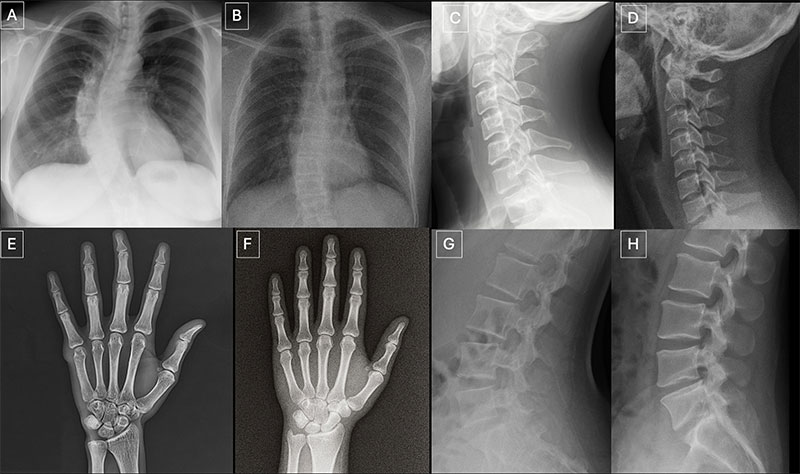

‘A contrast scan is a medical imaging test, such as a CT scan or MRI,’ says Dr Jean de Villiers, a radiologist and director of SCP Radiology, ‘that uses a special dye called a ‘contrast agent’ to make certain areas of the body easier to see. The contrast helps highlight blood vessels, organs or abnormal tissues, providing clearer and more detailed images. Dr de Villiers talks about the dye, what it is used for and debunks the myth that it is the iodine that causes allergic reactions in some people.

The contrast agent shows the blood flow through arteries and veins, blockages, bleeding or abnormal growths and detailed organ structure (such as the brain, liver or kidneys).

In short, contrast helps to highlight differences between normal and abnormal tissue, improving diagnosis and treatment planning.